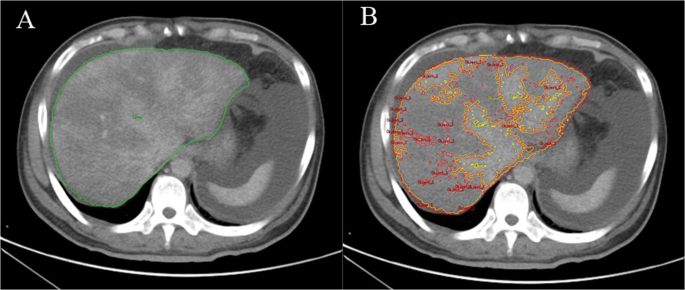

When employing the method to analyze the ROI of a lesion (ROIlesion), the threshold of the ROI of low-density areas (ROIlow density) and the ROI of the enhancement areas (ROIenhancement) were initially obtained. For the ROI low density, the threshold was obtained as [a, b] HU, while for ROIenhancement, the threshold was [c, d] HU. Then, we adjusted the threshold of the ROIlow density as [a, (b + c)/2)] and defined it as ROIlesion. The ROIlesion was regionally segmented, and the lesion area was then automatically measured using a computer to obtain the volumes of hepatic lesions. We also calculated the ratio of ROIlesion volume to ROIliver volume (Ratio). The ROIliver and ROIlesion of patients with PA-SOS were extracted by the threshold-based region growing algorithm (Fig. 3).

ROIs were extracted by the threshold-based region growing method (ROIliver, ROIlesion and ROIenhancement are represented by the green line, yellow line and red line, respectively): The volumes for (A) ROIliver and (B) ROIlesion were 2334821.84 mm3 (2.335 L) and 1650085.09 mm3 (1.650 L), respectively.